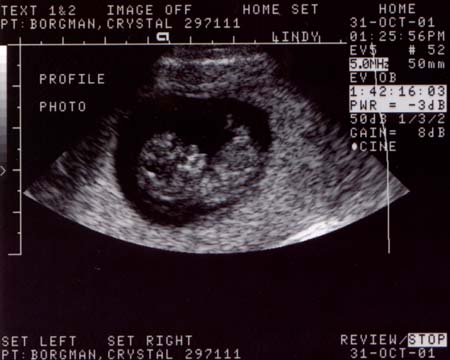

First ultrasound.

The baby looks great! It was moving around and having

a good old time. It measured at 10 weeks and 4 days,

or 37 millimeters (about 1 1/2 inches), which is just

about right. The heart rate was 188 bpm and very strong.

Looks like we've got a keeper.

Ultrasound Pictures:

Photo from top of

head looking down, baby's legs are crossed

Large

- 900x720 pixels / 66.1K

Small

- 450x360 pixels / 28.2K

head looking down, hands are together

- 900x700 pixels / 68K

- 450x350 pixels / 28.8K

Side profile, jaw

bones are prominent (the light areas)

- 900x720 pixels / 71.3K

- 450x360 pixels / 30.3K

Side profile, with

hand by face

- 900x600 pixels / 63.1K

- 450x300 pixels / 26.8K |